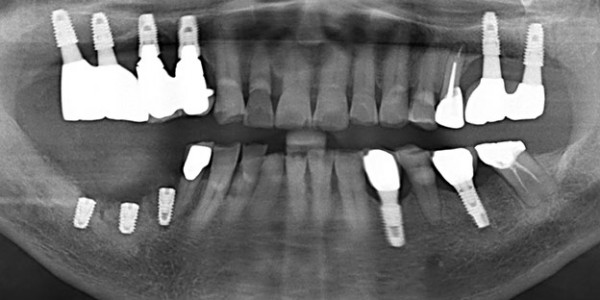

전체 임플란트 증례

→ SCROLL

전체임플란트 자세히보기    →

전체 임플란트 촬영날짜:

BEFORE

AFTER